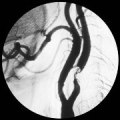

|

Operace krčních tepen |

Zalomení krční tepny |

Vyšetření